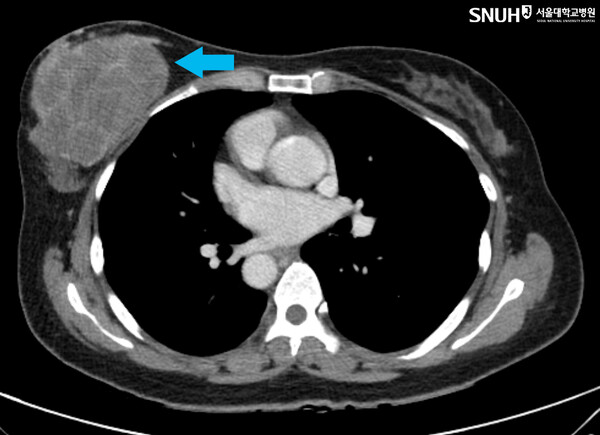

악성 엽상종은 성장이 빠르고 크기가 크며 재발과 전이가 잦다. 그러나 지금까지 수술 외에는 효과적인 치료법이 없고, 연구를 위한 적절한 세포주와 동물모델도 부족해 치료제 개발에 난항을 겪고 있었다.